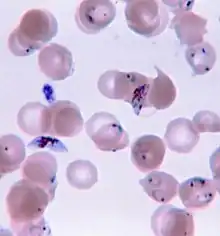

| Malaria parasite connecting to a red blood cell | |

Malaria is usually confirmed by the microscopic examination of blood films or by antigen-based rapid diagnostic tests (RDT). Microscopy – i.e. examining Giemsa-stained blood with a light microscope – is the gold standard for malaria diagnosis.[33] Microscopists typically examine both a "thick film" of blood, allowing them to scan many blood cells in a short time, and a "thin film" of blood, allowing them to clearly see individual parasites and identify the infecting Plasmodium species.[33] Under typical field laboratory conditions, a microscopist can detect parasites when there are at least 100 parasites per microliter of blood, which is around the lower range of symptomatic infection.[62] Microscopic diagnosis is relatively resource intensive, requiring trained personnel, specific equipment, electricity, and a consistent supply of microscopy slides and stains.[62]